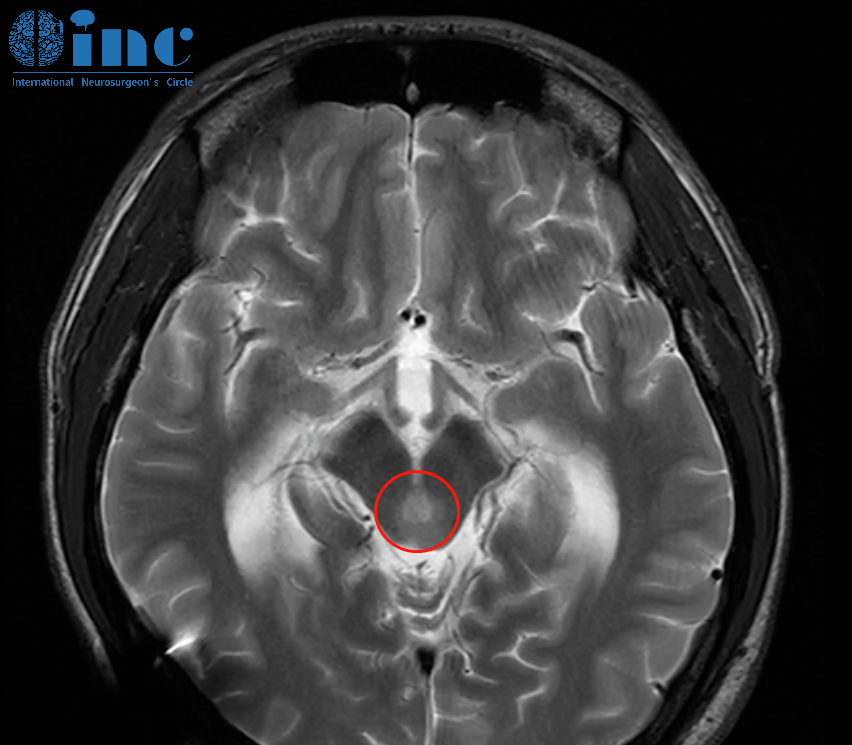

8月17日,巴教授還為一名腦干海綿狀血管瘤患者順利手術(shù)。這位28歲的吳先生無疑是幸運(yùn)的,在腦干海綿狀血管瘤還處于萌芽階段時(shí),就被及時(shí)發(fā)現(xiàn)并交由巴教授完成精準(zhǔn)切除,消除了再次出血的風(fēng)險(xiǎn)。術(shù)前,渴望早日回歸正常生活的吳先生堅(jiān)定地表示,“我對(duì)教授非常有信心!”年輕的他,再也無法忍受終日擔(dān)憂出血的煎熬。

影像

示范手術(shù)在蘇州大學(xué)附屬第四醫(yī)院成功開展。吳先生的病灶位于大腦腳中腦腹側(cè)面,緊鄰腳間窩,解剖位置極為復(fù)雜: